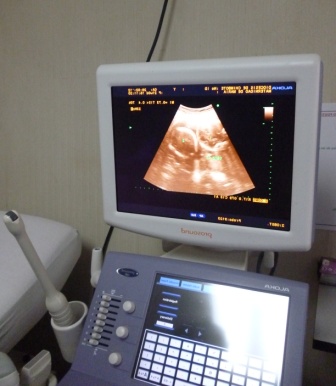

Chimbotenlinea.com(Redacción central).-El Centro de Obras Sociales, Maternidad de María, cuenta con dos modernos equipos ecógrafos y brinda este servicio a la comunidad con la garantía de que los exámenes son realizados por médicos de reconocida trayectoria en nuestra localidad. Estos equipos son muy útiles ya que ayuda la detección de enfermedades, entre ellas el temido cáncer.

Este servicio es muy acogido en la Maternidad de María por su bajo costo, su implementación de última generación y el excelente personal profesional;  las ecografías 3D y 4D son muy requeridas por las madres gestantes, ecografías transvaginales y examen de mamas, entre otras.

Este equipo  cuenta  con  un  transductor o sonda conectado a un monitor por un cable. El transductor o sonda es un dispositivo parecido a un micrófono.

El radiólogo administra un gel sobre la zona a explorar y aplicará la sonda sobre la piel. La imagen aparece inmediatamente en la pantalla. A veces la propia paciente puede ver el monitor.